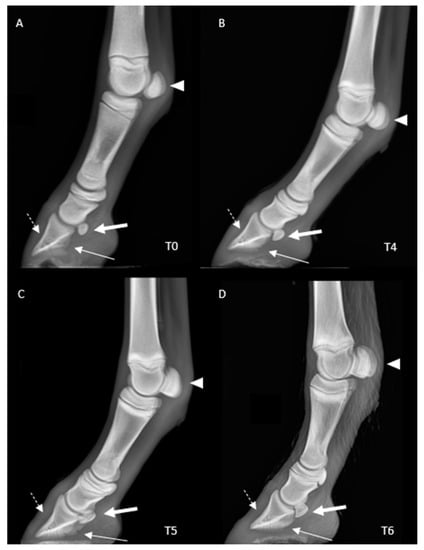

Radiographic Appearance of the Fore Digit and Carpal Joint in the Mule Foal from Birth to 3 Months of Age